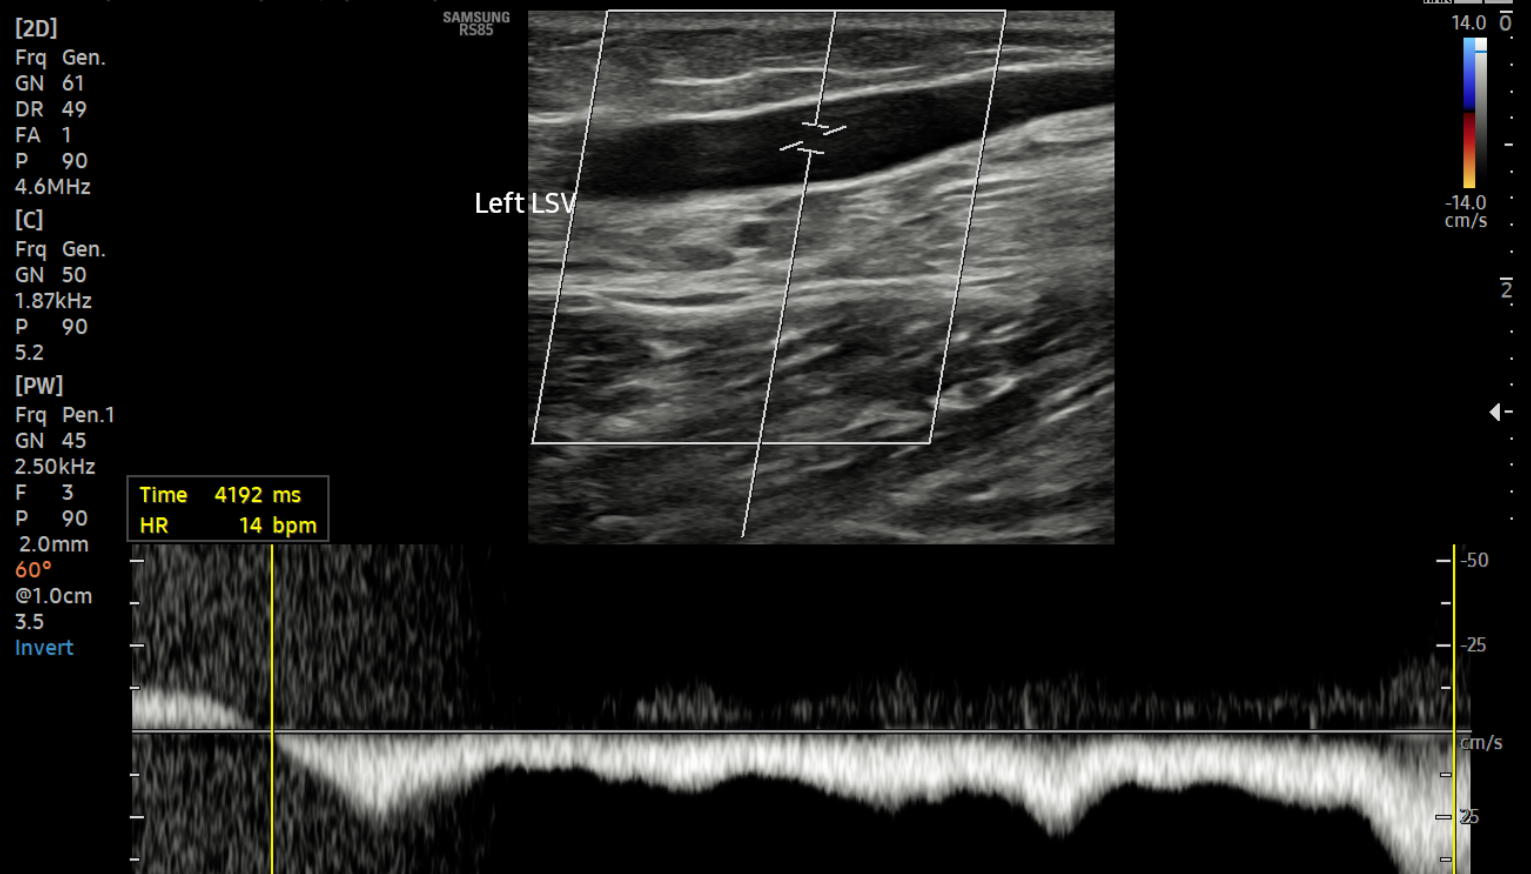

What does a duplex ultrasound actually show

A duplex ultrasound provides real‑time information about both vein structure and blood flow. It allows assessment of whether blood is flowing in the correct direction, how long reflux persists, and which veins are involved. It also distinguishes between superficial and deep venous disease and identifies anatomical variations that influence treatment planning.

Importantly, duplex ultrasound also confirms that the deep venous system is functioning normally and excludes obstruction or thrombosis. This information is essential for safe treatment and cannot be inferred without imaging.